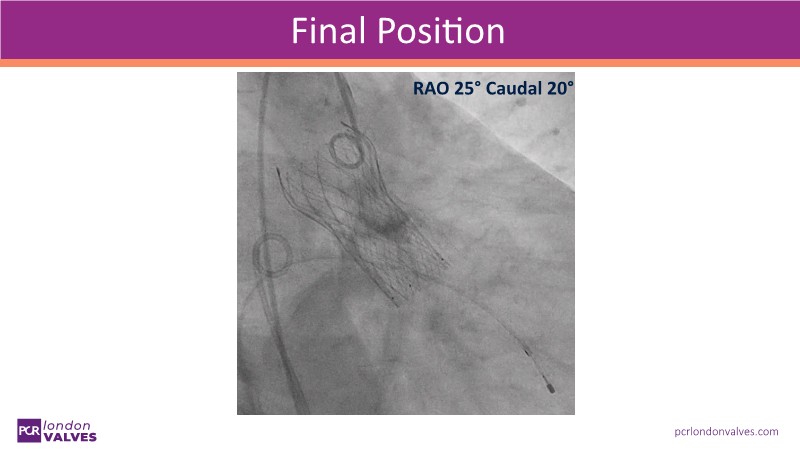

- To learn how to perform TAVI resulting in commissural alignment and easier coronary access